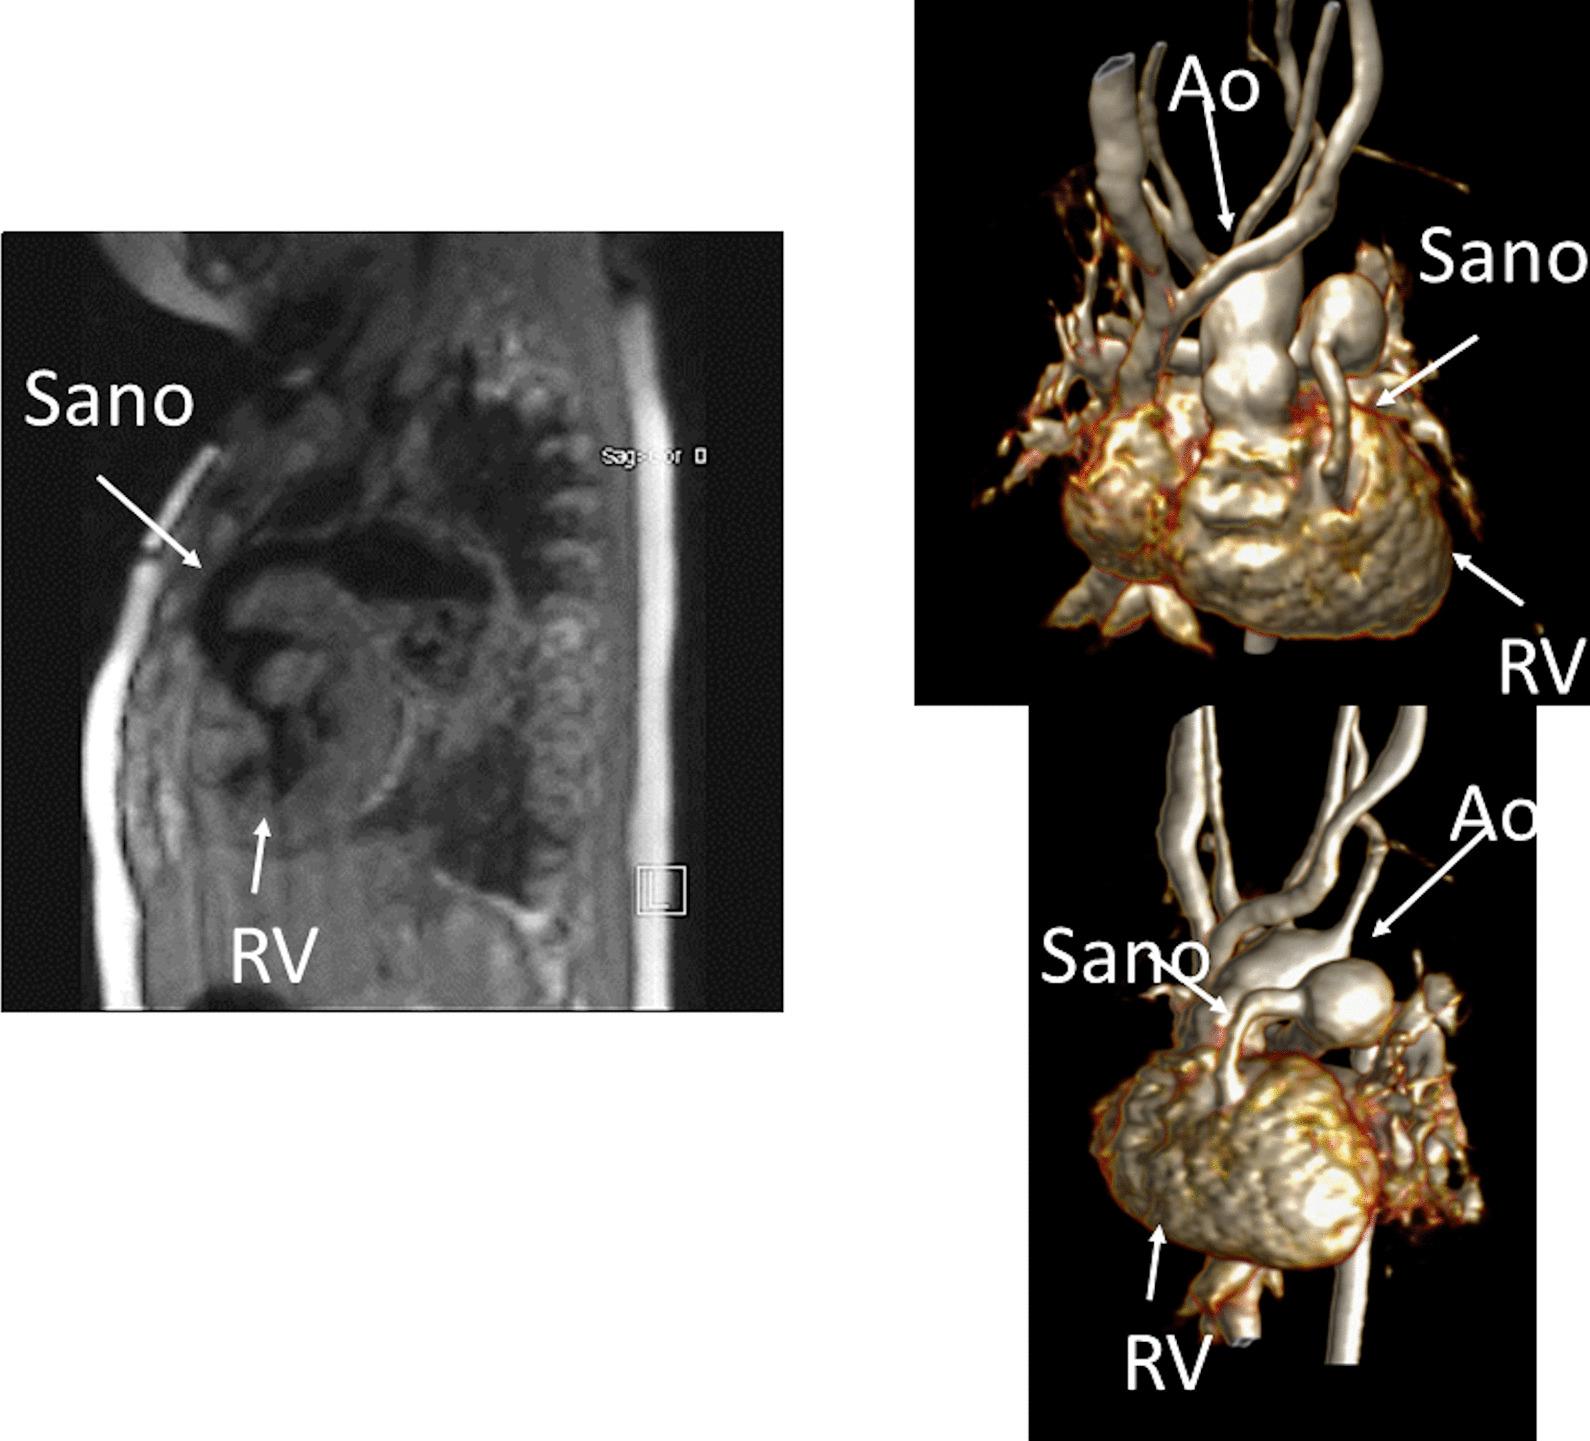

Cardiovascular magnetic resonance (CMR) has been utilized in the management and care of pediatric patients for nearly 40 years. It has evolved to become an invaluable tool in the assessment of the littlest of hearts for diagnosis, pre-interventional management and follow-up care. Although mentioned in a number of consensus and guidelines documents, an up-to-date, large, stand-alone guidance work for the use of CMR in pediatric congenital 36 and acquired 35 heart disease endorsed by numerous Societies involved in the care of these children is lacking. This guidelines document outlines the use of CMR in this patient population for a significant number of heart lesions in this age group and although admittedly, is not an exhaustive treatment, it does deal with an expansive list of many common clinical issues encountered in daily practice.

心血管磁共振(CMR)在儿科患者的管理和护理中已经应用了近 40 年。它已经发展成为评估最小的心脏的宝贵工具,用于诊断、介入前管理和随访。尽管在许多共识和指南文件中提到,但在儿科先天性心脏病和后天性心脏病领域,目前还缺乏一份由众多参与儿童护理的学会共同认可的、最新的、独立的、针对 CMR 使用的大型指南。本指南文件概述了 CMR 在该年龄段的许多心脏病变中的应用,尽管不能说是详尽的治疗方法,但它确实涉及了在日常实践中经常遇到的许多常见临床问题的广泛列表。